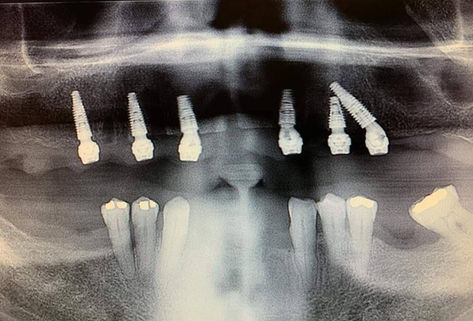

3rdSET Implant Solutions is a Nevada based corporation and its members are licensed dentists in Nevada and Arizona. 3rdSET® Implant Solutions is part of a professional affiliation of dental practices that provide implant dentistry within their local practices which delivers restorative dentistry.